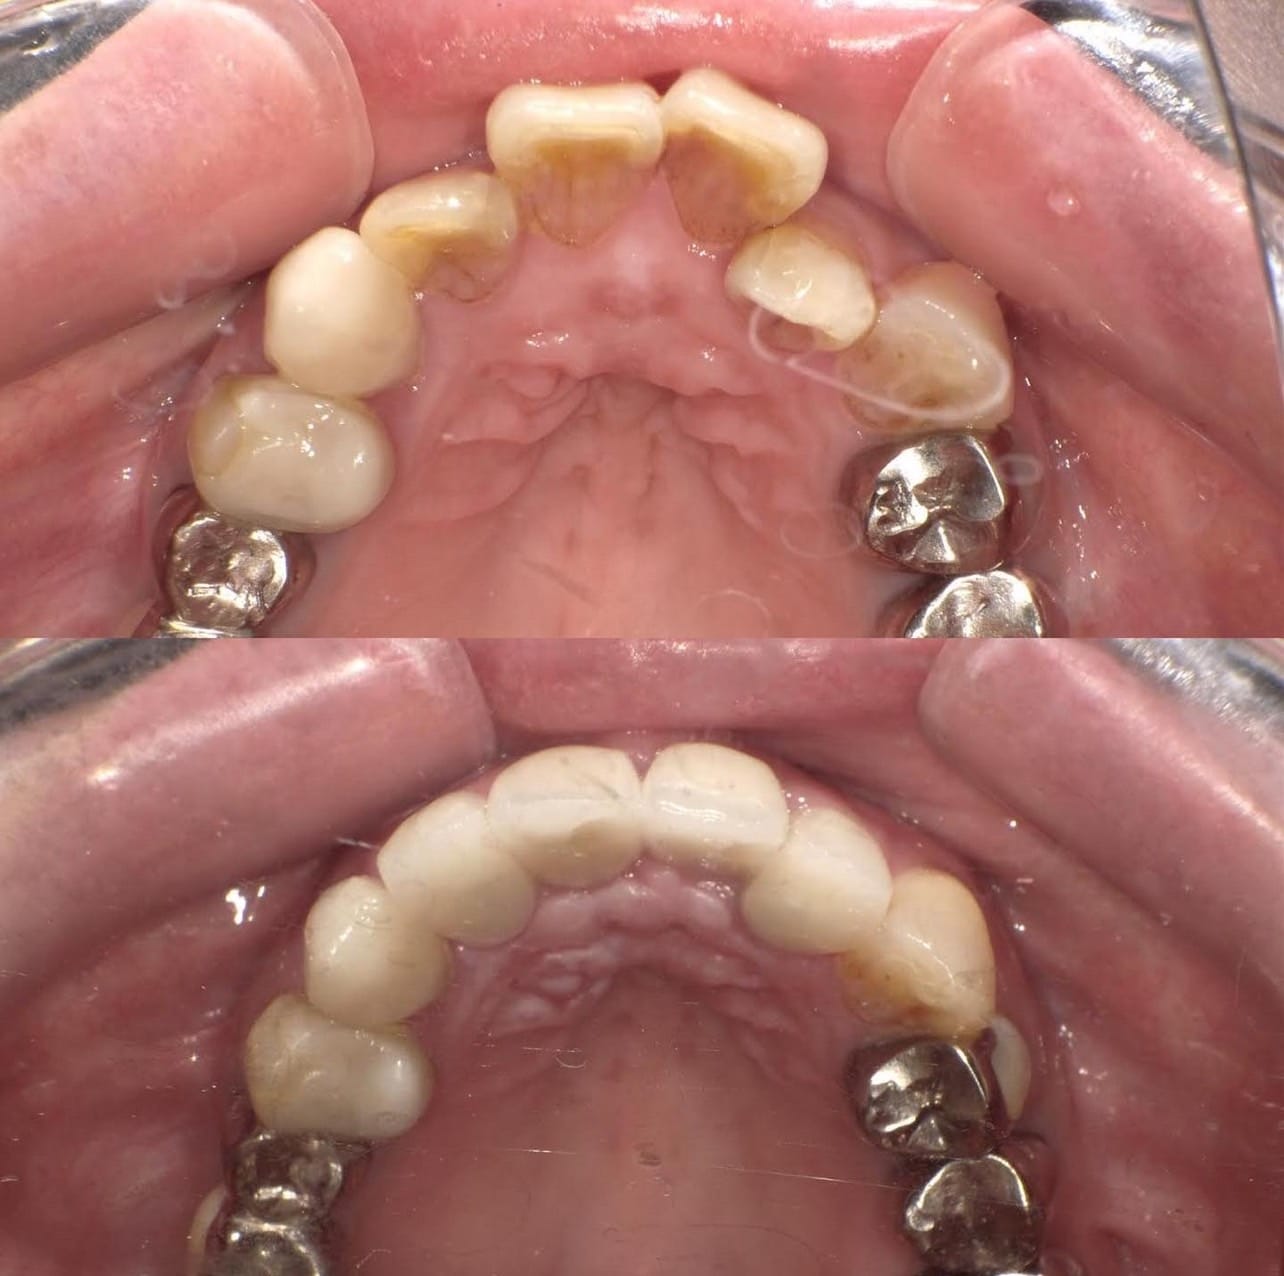

前歯が虫歯なのと、保険のプラスチックで大きく治療されていて色が悪いこと、歯並びが出っ歯気味であることを気にしてセラミックにしたいという主訴で来院された患者様です。

虫歯が大きかったところは神経治療をきちんと行い、

初診時を含めてトータル4回のご来院で完了です。

今回は前歯を下げる、歯列を整える、白すぎず自然に綺麗に見える色というご希望に沿って治療しました。